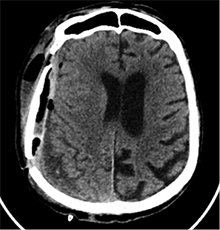

53 m. vyras sumuštas gatvėje ir greitosios medicinos pagalbos atvežtas į Priėmimo skyrių. Pacientui atlikta galvos kompiuterinė tomografija (GKT). Rasta: poūmė, stora, apie 16 mm dydžio subdurinė hematoma (SDH) dešinėje pusėje konveksitaliai ir ūmi nedidelė SDH kairėje pusėje frontoparietaliai. Vidurio struktūrų dislokacija (VSD) į kairę – minimali. Kairėje – kaukolės skliauto linijinis lūžis. Nustatyta nosies kaulų, nosies pertvaros, dešiniojo viršutinio žandikaulio kaktinės ataugos ir kūno, sinuso sienelių lūžių, dešinės akiduobės medialinio krašto lūžių ir dešiniojo skruostinio lanko lūžių (1 pav.). 2020 m. liepos mėn. pacientas skubos tvarka operuotas: atlikta dešinė kraniotomija, pašalinta hematoma. Atlikus kontrolinę GKT, buvo matyti, kad pašalinta didžioji hematomos dalis (2 pav.). Pacientas konsultuotas veido ir žandikaulio chirurgo, skubus chirurginis gydymas neindikuotas. Praėjus 3 savaitėms, pacientas, esant gerai funkcinei ir neurologinei būklei, tolesnio gydymo perkeltas į slaugos ligoninę, vėliau išleistas gydytis ambulatoriškai.

1 pav. Prieš pirmąją operaciją (poūmė, stambi, iki 16 mm SDH apie dešinįjį pusrutulį, ūmi nedidelė SDH kairėje F-P; VSD į kairę ~3 mm)